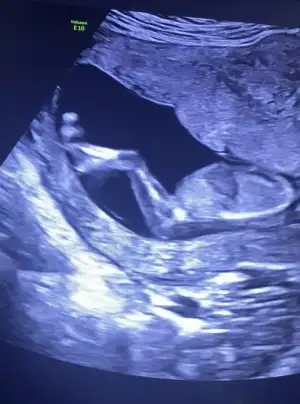

ErkekmiErkek tabiki en iyi 11 12 13 haftalar olmalı

Ama sag duvara yapisiksa kiz sol duvara yapisiksa erkek derler bu saga yapisik?Erkek tabiki en iyi 11 12 13 haftalar olmalı

Karında olsa sağ kız sol erkek vajinal da sağ erkek sol kız 6 yıldır burdayım tabi en iyi 11 12 13 haftalarVajinal aynalama olur benim.oglum oldu ilk onunki sol duvardaydi yine vajinalden

Benim anladigim bebegin kese icindeki konumu önemli kesenin rahimdeki konumu degil degilmiDedimya en iyi 11 12 13 haftalar olmalı kese konumu herzaman tutmuyor

Evet kese içindeki yolk saç önemliBenim anladigim bebegin kese icindeki konumu önemli kesenin rahimdeki konumu degil degilmi

Erkek diyorumIkra meyra banana tahmin yapabilir misiniz?14 haftalık ultrasonŞimdiden teşekkür